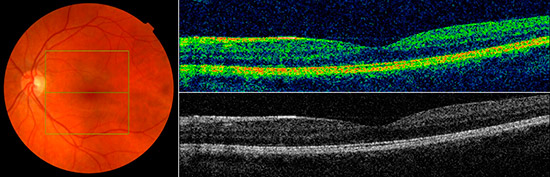

Estado normal de la mácula

Estado normal de la mácula vista con OCT.